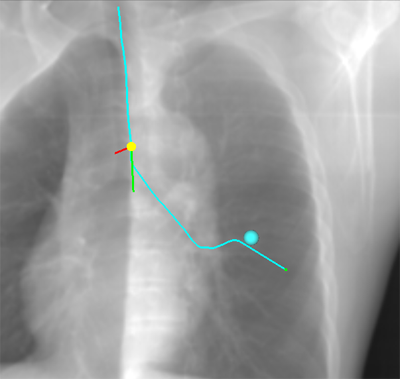

CTデータから疑似X線透視画像を生成し、仮想気管支鏡位置と合成表示することが可能です。

疑似X線透視画像とナビゲーション画像と連動させることで、気管支鏡の位置把握をタイムリーに行うことができます。

DirectPathはCT画像上で指定した病変にアプローチする経路を自動生成し、3Dの仮想気管支鏡画像で表示します。